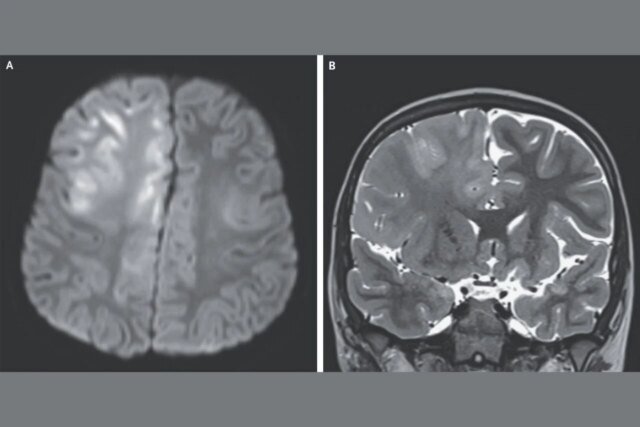

Nesse caso, o menino de 7 anos visitou o médico três meses depois de ter convulsões e declínio cognitivo. Ele não conseguia mais falar e uma ressonância magnética (vista na imagem superior) revelou extensos danos ao cérebro. O menino contraiu sarampo aos 7 meses de idade enquanto vivia no Afeganistão, país onde o vírus é endêmico. Testes de seu líquido espinhal revelaram altos níveis de anticorpos contra o vírus do sarampo. Isso, juntamente com seu histórico de infecção e resultados de EEG, levou os médicos a diagnosticá-lo com SSPE.